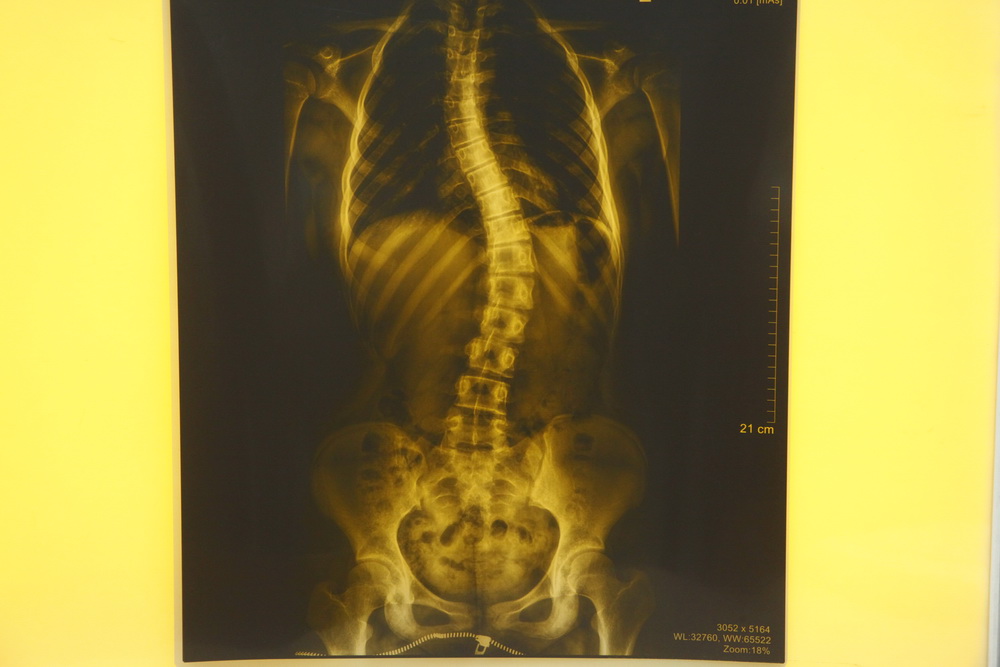

Рентгеновский снимок с искривлением позвоночника. Фото: Евгений Аникеев, nsknews.info

По словам руководителя, основное заболевание, с которым работает организация, — идиопатический сколиоз. Это сложная патология позвоночника, причина которой до конца не понятна, известно лишь, как развиваются и из чего складываются деформации.